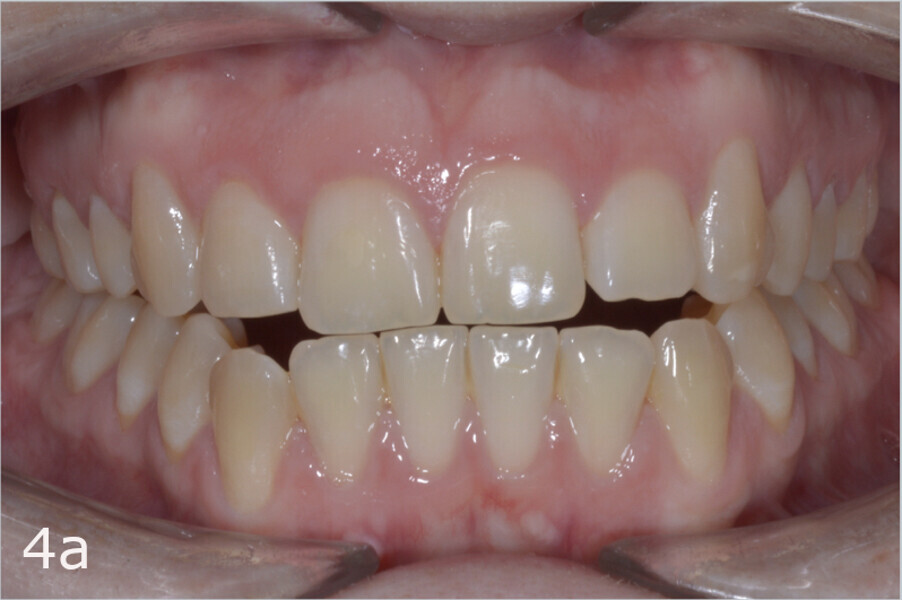

The 23-year-old dolichofacial female patient complained of not being able to chew properly. Facial examination showed a convex profile, an enlarged lower facial height, and a skeletal Class III malocclusion (Figs. 1–3). Intra-oral examination revealed an Angle Class III right subdivision malocclusion, anterior open bite, no overjet and a maxillary dental midline deviated about 3 mm to the right compared with the mandibular dental midline (Fig. 4). The panoramic radiograph confirmed previous extraction of the maxillary right first premolar and the presence of all four third molars (Figs. 5 & 6).

The treatment objectives included closing the anterior open bite, achieving a bilateral Angle Class I relationship and a proper overjet and overbite, correcting the midline discrepancies, and achieving a profile harmonisation. The treatment plan consisted of orthodontic camouflage treatment with asymmetric distalisation in three of the four quadrants using Invisalign aligners (Align Technology) and third molar extraction. The Invisalign Comprehensive package was chosen, and 63 pairs of aligners were used (Figs. 7–10). Each aligner was worn for 20 hours a day for one week each. The use of Class III elastics on both sides was indicated. Afterwards, ten refinement aligners were needed to improve the interdigitation on the right side (Figs. 11 & 12).